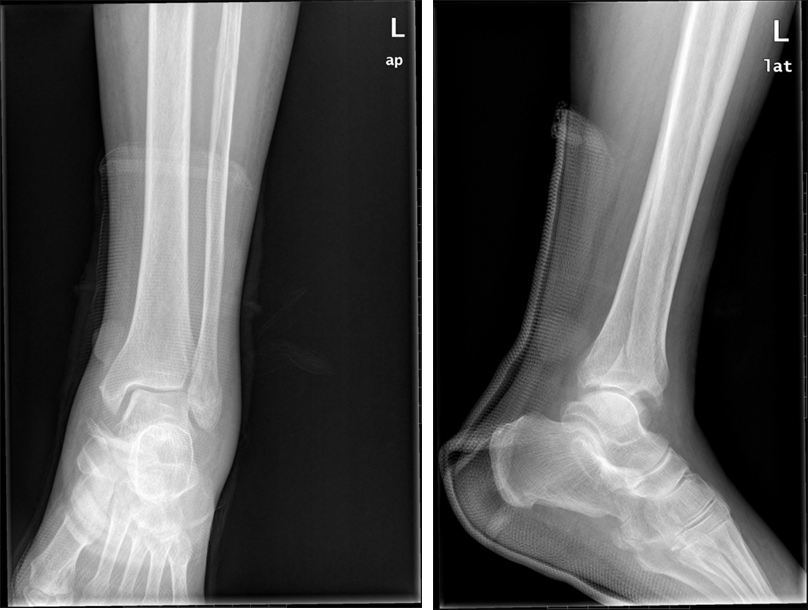

就医后,医生通常会进行 X 线、CT 或磁共振成像(MRI)等检查,以明确损伤的程度和类型,并制定相应的治疗方案。对于轻度和中度扭伤,一般采用保守治疗,如佩戴踝关节固定支具、物理治疗等;对于重度扭伤,可能需要进行手术治疗,修复断裂的韧带。